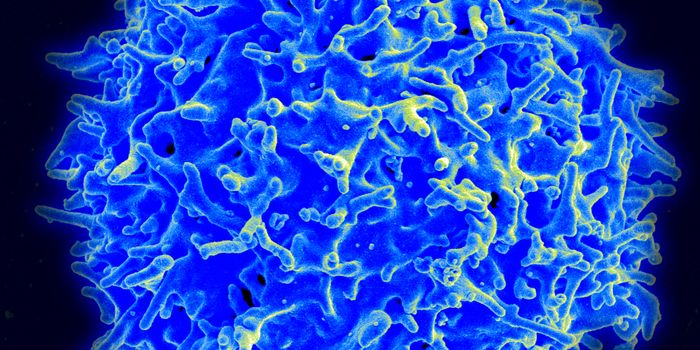

SEP 30, 2015ImmunologyCurrently in the United States, 13 percent of the 1.2 million people infected with HIV are unaware of their condition (A ...